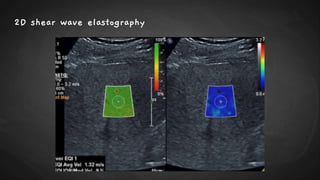

2D shear wave elastography

● SWE can be performed using acoustic radiation force impulse (ARFI) technology either in a

1. Point–shear wave elastography, (p-SWE) small region of interest (ROI) or

2. Two-dimensional shear wave elastography [2D-SWE] over a larger field of view using

color-coding to visually display the stiffness values